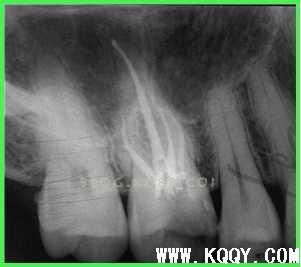

逐步后退法:适用于直或者轻中度弯曲根管

1:根管下三分之一:初锉到达生理性根尖孔假定10号

顺序10-15-10-20-15-25-20 25为主尖锉

冲洗很重要!!!!

中段:每增大一号退1MM,但都必须用主尖锉到达工作长度

上段:G钻

最后25号锉锉平台阶。

优点:不易损伤根尖,不易超充